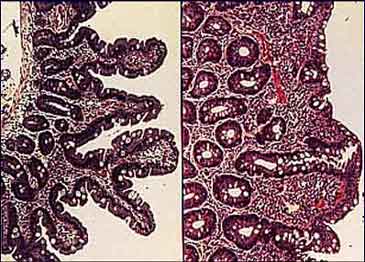

This image illustrates the shape and components of a healthy mucosal barrier. In the image below, we see a healthy mucosal lining (left) and one with collapsed tissues—caused by inflammation—on the right. When the finger-like projections called villi collapse visible on the right—harmful organisms are harbored and given a safe place to thrive, while nutrient absorption becomes compromised. The promotion of healing and protection against such damage is paramount to overall health and disease prevention.